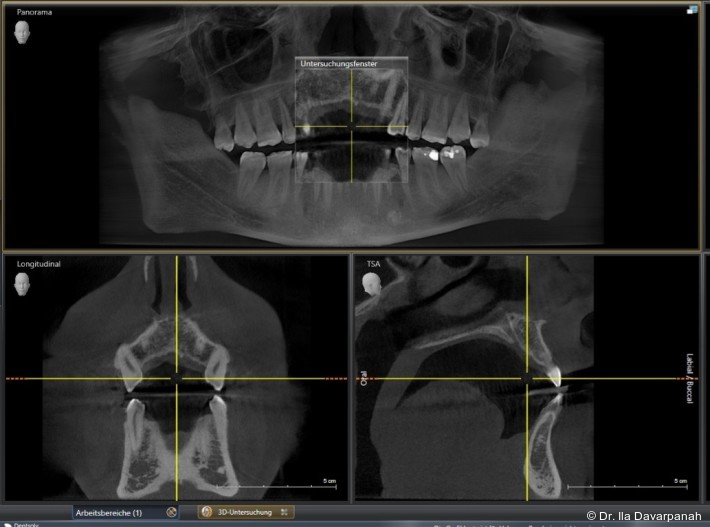

Neben patientenbezogenen und chirurgischen Faktoren spielt dabei auch das Implantatdesign eine wesentliche Rolle. Die vorliegende Falldokumentation zeigt eine Sofortimplantation Regio 11 mit digitaler Planung anhand von DICOM- und STL-Daten. Die präoperative Planung erfolgte softwaregestützt, die Implantatposition wurde prothetisch orientiert festgelegt. Klinisch und radiologisch lagen günstige Ausgangsbedingungen für eine Sofortimplantation mit Sofortversorgung vor.

Postoperativ kam es trotz korrekter Implantatpositionierung und regelrechter Sofortversorgung zu einer Fraktur des Implantatkörpers im Bereich der Implantatschulter. Die radiologische Diagnostik mittels Röntgen und DVT zeigte ein Aufplatzen des Implantats im Übergangsbereich zwischen Konusverbindung und Implantatplattform. Das Frakturmuster deutete auf eine strukturelle Überlastung im hoch beanspruchten Schulterbereich hin. Implantatfrakturen stellen insgesamt eine seltene, jedoch für Patient und Behandler belastende Komplikation dar. Sie treten bevorzugt in Regionen mit erhöhten Biege- und Querkräften auf, insbesondere in der Frontzahnregion und bei frühzeitiger funktioneller Belastung.